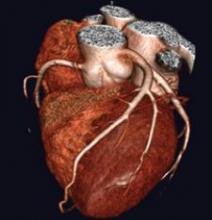

The compact ProSound Alpha 7 ultrasound system from Aloka features Directional eFLOW, which visualizes blood flow dynamics from low to high velocity flow reportedly without overlapping and with a high degree of accuracy. Also included are basic imaging performance enhancements with Broadband Harmonics, ExPHD (Extended Pure Harmonic Detection) and high temporal resolution to aid in the diagnoses of fetal heart conditions.